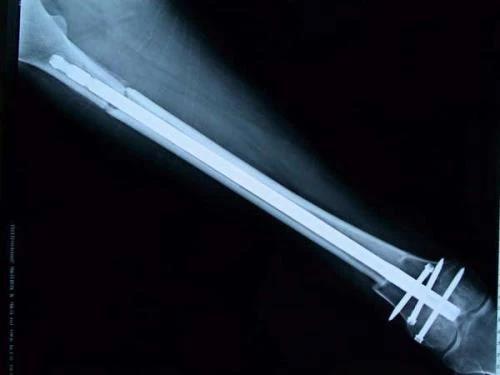

保肢治療指經(jīng)典型骨肉瘤在多學(xué)科團(tuán)隊(duì)醫(yī)生共同努力下完成的新輔助化療、保肢手術(shù)和輔助化療等一系列治療總稱,其目的是在提高患者生存率的前提下,減少局部復(fù)發(fā)、盡量保留良好的肢體功能。肢體經(jīng)典型骨肉瘤保肢治療方法如下圖所示:

新輔助化療的目的是盡早殺滅遠(yuǎn)處微小轉(zhuǎn)移灶,縮小腫瘤及周圍炎性水腫反應(yīng)區(qū),以利于后續(xù)的保肢手術(shù);觀察腫瘤對(duì)化療的敏感性,為進(jìn)一步指定個(gè)體化的術(shù)后化療方案奠定基礎(chǔ)。骨肉瘤新輔助化療下的保肢治療如下圖所示: